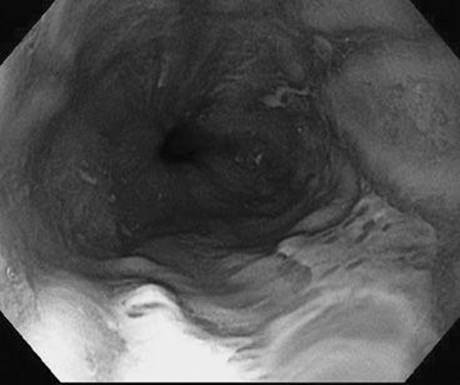

In a patient with melena but a normal hematocrit, the lesion below was found on upper endoscopy. Based on its appearance, what is the approximate risk of rebleeding from this lesion?

Figure 1-3 See also color plate.

The risk of rebleeding in an ulcer with a flat pigmented spot is about 10%.